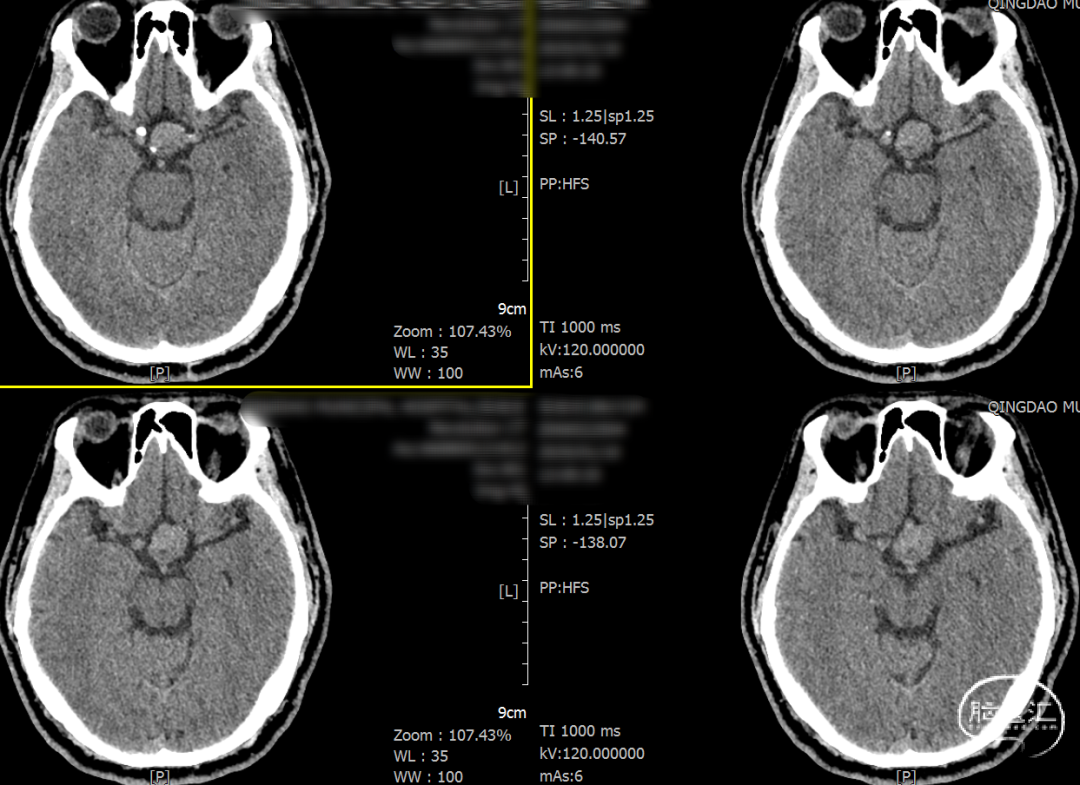

2025-1-19 DSA造影3D重建及方案讨论:

DSA造影3D重建测量

2.5mm*15mm Surpass Evolve密网支架,支架锚定区为右侧A2~A1

造影确认远端打开良好,定位后完全释放支架。

支架置入后造影显示,瘤内滞留明显,对侧造影几乎未见瘤内造影剂显影,手术结果满意。